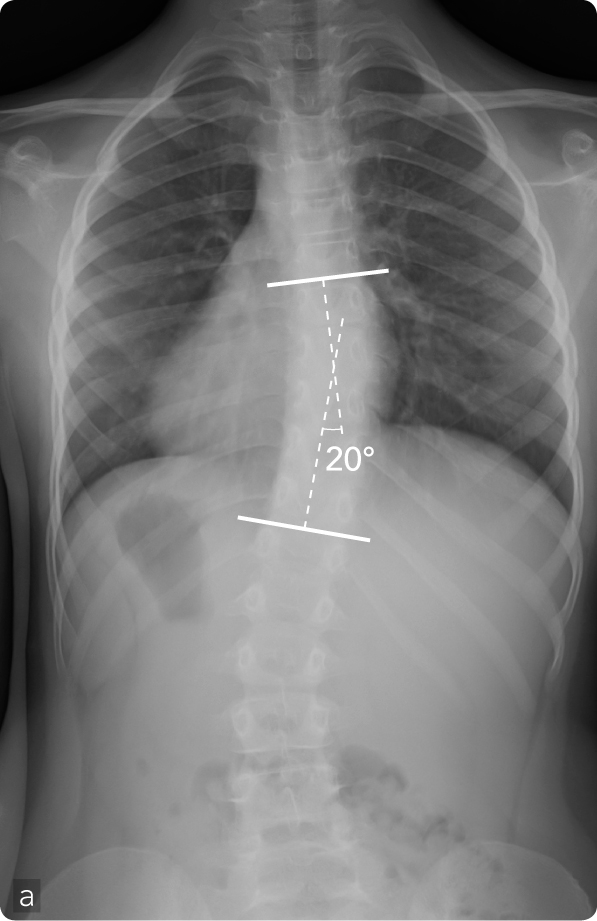

Femmina, 8 anni, scoliosi dorsale destra (a). Asimmetria del profilo delle scapole e dei fianchi (b) ed evidente gibbo dorsale destro (c). Trattamento con busto gessato in deflessione (d). Obiettiva riduzione del gibbo ai controlli successivi in particolare alla flessione anteriore del tronco (e) confermata dal controllo radiografico (f).